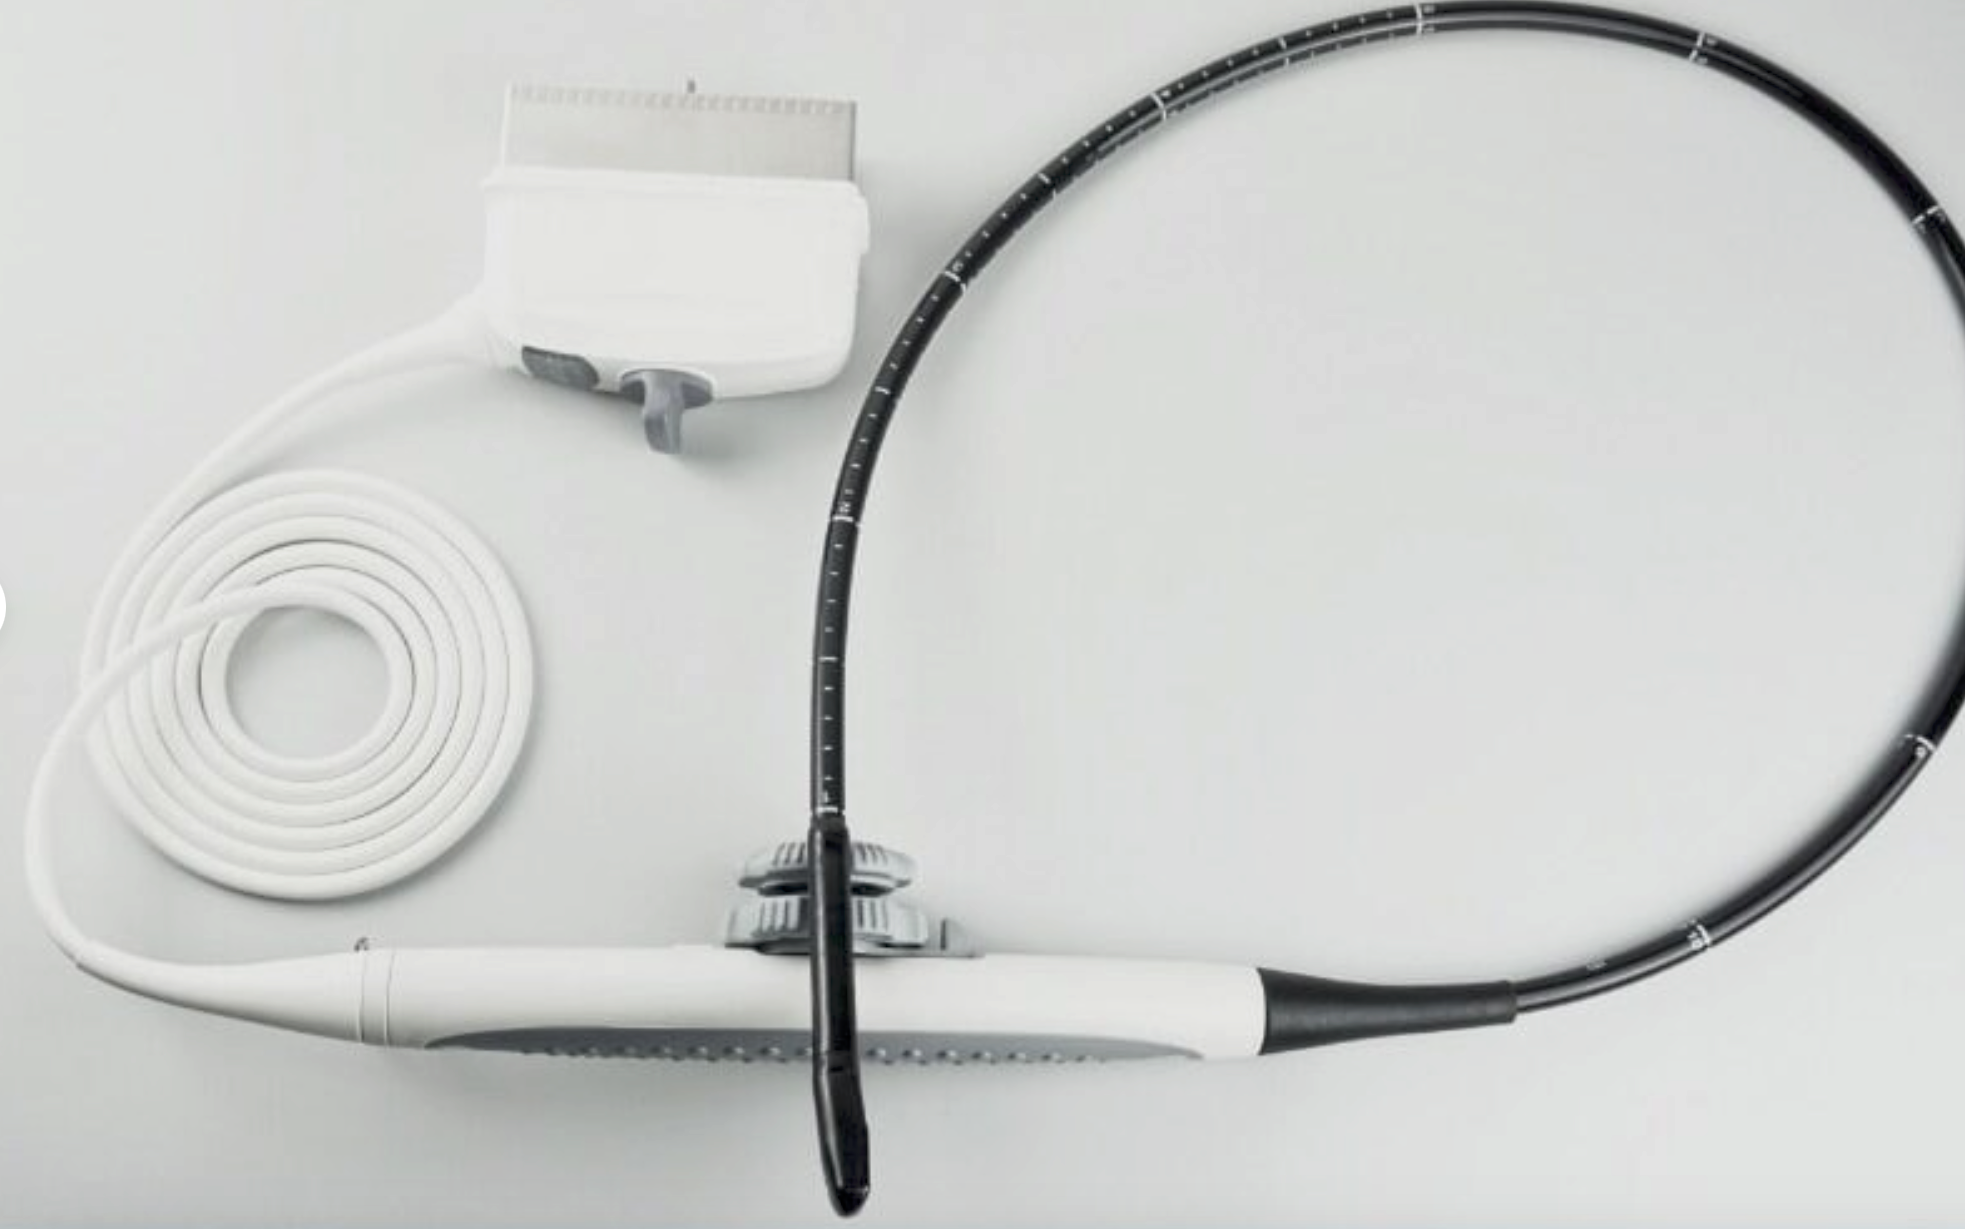

Versatile Probes for Different Needs

Equipped with the S3-1 and L9-3 transducer probes, the Philips IU22 offers versatility that caters to diverse clinical needs. The S3-1 probe is excellent for abdominal and obstetric examinations, while the L9-3 probe specializes in cardiac imaging. Additionally, these probes are designed for user comfort, reducing the strain during prolonged procedures. Thus, healthcare professionals can provide more efficient and comfortable patient care.